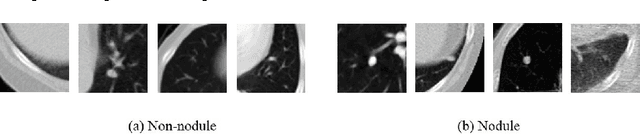

Abstract:Lung nodule classification is a class imbalanced problem, as nodules are found with much lower frequency than non-nodules. In the class imbalanced problem, conventional classifiers tend to be overwhelmed by the majority class and ignore the minority class. We showed that cascaded convolutional neural networks can classify the nodule candidates precisely for a class imbalanced nodule candidate data set in our previous study. In this paper, we propose Fusion classifier in conjunction with the cascaded convolutional neural network models. To fuse the models, nodule probabilities are calculated by using the convolutional neural network models at first. Then, Fusion classifier is trained and tested by the nodule probabilities. The proposed method achieved the sensitivity of 94.4% and 95.9% at 4 and 8 false positives per scan in Free Receiver Operating Characteristics (FROC) curve analysis, respectively.

Abstract:Lung nodule classification is a class imbalanced problem because nodules are found with much lower frequency than non-nodules. In the class imbalanced problem, conventional classifiers tend to be overwhelmed by the majority class and ignore the minority class. We therefore propose cascaded convolutional neural networks to cope with the class imbalanced problem. In the proposed approach, multi-stage convolutional neural networks that perform as single-sided classifiers filter out obvious non-nodules. Successively, a convolutional neural network trained with a balanced data set calculates nodule probabilities. The proposed method achieved the sensitivity of 92.4\% and 94.5% at 4 and 8 false positives per scan in Free Receiver Operating Characteristics (FROC) curve analysis, respectively.